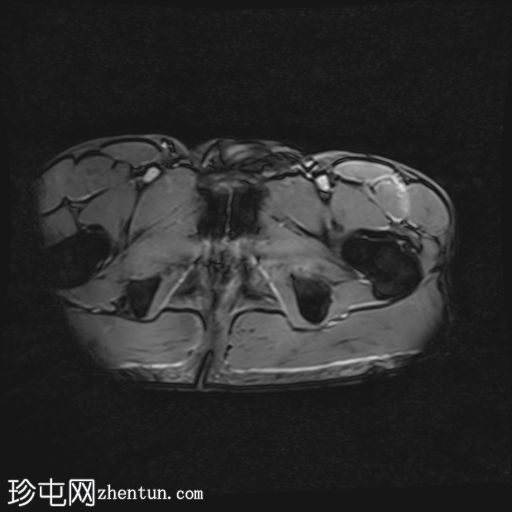

轴位

T1加权像

股直肌近端和中段前外侧可见一水肿性高信号影,长约15厘米,宽约3厘米。肌纤维轻度分离,但未见撕裂。肌内未见积液;在相邻肌间隙可见一条细小的液线环绕肌肉,延伸至近端肌腱交界处。

股直肌中段的间接肌腱轻度增厚,伴有肌腱周围水肿,提示2B级拉伤。但肌腱保持连续性,骨性附着良好,未见撕裂。